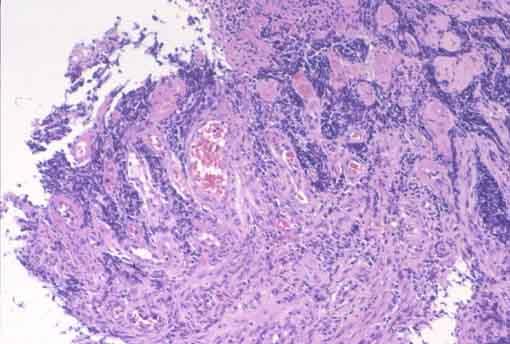

Criteria of Hist.ClassificationMalignant epithelial tumor/Undifferentiated carcinoma

LocationEsophagus/More than one of the above

Technique, MethodHistology

Macroscopic TypesType 5 Unclassfied type/

Size40 -